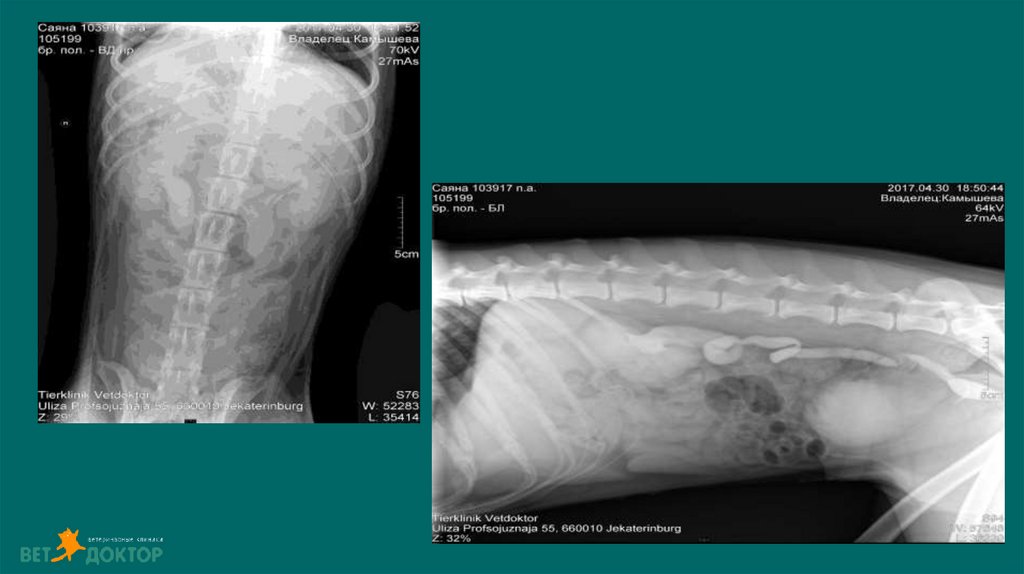

8. Диагностика

6. Рентгенологические исследования

Размер и симметричность почек, размер и топографию мочевого пузыря, размер и

положение репродуктивных органов.

У собак почки имеют бобовидную форму. Размер в 2,5-3,5 раза превышают длину L 2

У кошек овальная до круглой. Размер почек измеряют на ВД проекции в 2,4-3,0 раза

превышают длину L2

Размер проксимального отдела мочеточника :

Собаки 2-3мм. Кошки 1-2мм

Метод выявления рентгеноконтрастных уролитов (фосфат кальция, оксалат кальция,

струвиты)

Ураты /цистеиновые уролиты рентгенопрозрачны.